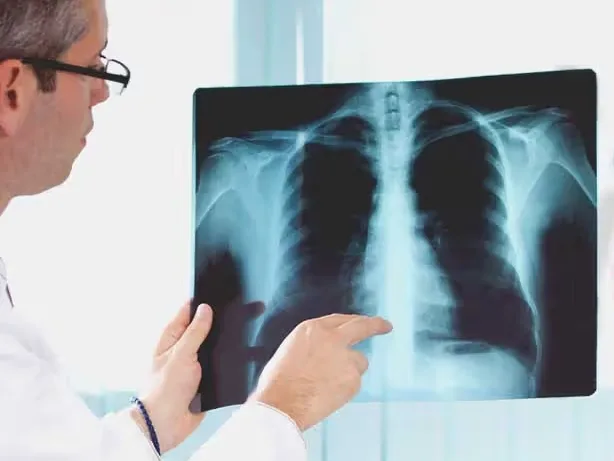

وادی میں نمونیا کے شکار بچوں کی شرح ہر سال بڑھ رہی ہے اور اکتوبر کے مہینے سے ہی بچے وائرل انفیکشن کے شکار ہوجاتے ہیں۔سرکاری اعدادوشمار کے مطابق وادی میں نمونیا کے سب سے زیادہ متاثرین کولگام میں 20.3فیصددرج ہوئے ہیں۔پھیپھڑوں میں موجود سانس کی نلیوں میں انفیکشن کی وجہ سے پیدا ہونے والی سوجن کو نمونیا کہتے ہیں ۔ نمونیا کی بڑی وجوہات میں دمہ،پھیپھڑوں کی مانس پیشیوں میں بیماریاں اور دیگر وجوہات ہیں،جن میں بچوں کو دودھ نہ دینا اور بروقت ٹیکہ کاری نہ کرنا شامل ہے۔ کشمیر یونیورسٹی کے پاپولیشن ریسرچ سینٹر کی جانب سے 5سال تک کے بچوں پر کی گئی تحقیق میں یہ بات سامنے آئی ہے کہ بچوں میں نمونیا کی اصل وجوہات میں خوارک کی کمی، نامکمل ٹیکہ کاری، گھروں میں کھانہ پکانے کیلئے بالن اور دیگر ٹھوس ایندھن کا استعمال، بھیڑ بھاڑ، بچوں کو ماں کا دودھ نہ دینا، مائوں میں تعلیم کی کمی اور دیگر معاملات شامل ہیں۔ تحقیق کے مطابق آمدن کے محدود وسائل اور دیگر جیناتی وجوہات کی وجہ سے بھی بچوں میں نمونیا ہوجاتاہے۔ مختلف اضلاع کے اعداد و شمار فراہم کرتے ہوئے تحقیق میں بتایا گیا ہے کہ اننت ناگ ضلع میں 2.9 فیصد،بانڈی پورہ میں 0.5، بارہمولہ میں 0.9، کولگام میں20.3، کپوارہ میں 2.4،پلوامہ میں 1.37، شوپیان میں 0.9اور سرینگر میں 0.4فیصد بچے نمونیا کے شکار ہوتے ہیں جبکہ گاندربل اور بڈگام ضلع میںبچوں میں نمونیا کی بہت کم شرح پائی گئی۔ جموں صوبے کے ڈوڈہ میں 1.1فیصد، جموں میں 0.9،پونچھ میں 0.9، راجوری میں 1.69، رام بن میں 1.09، ادھمپور میں 0.8، ریاسی 2.01، جبکہ کٹھوعہ اور سانبہ میں نمونیا کی کم شرح دیکھی گئی۔ سکمز صورہ میں پھیپھڑوں کی بیماریوں کے ماہر ڈاکٹر مدثر قادری نے کشمیر عظمیٰ کو بتایا کہ پہلے بچوں کیلئے ماں کا دودھ جڑی بوٹی کا کام کرتا ہے جو نوزائید بچوں کو مختلف بیماریوں سے لڑنے کی طاقت دیتا ہے اور جن بچوں کو مائیں اپنا دودھ نہیں پلاتی ہیں وہ اکثر چھاتی کی مختلف بیماریوں کے شکار ہوجاتے ہیں۔ انہوں نے کہا کہ اس کے علاوہ مختلف ویکسین بچوں کو دینا اسلئے بھی ضروری ہوتا ہے کیونکہ یہ بچوں کو چھاتی کی بیماری سے بھی بچاتا ہے ۔ انہوں نے کہا کہ خاصکر انفیکشن (نمونیا )سے بچاتا ہے۔ انہوں نے کہا کہ بچوں اور عمر رسیدہ افراد کو موسم سرما سے بچنے کی کوشش کرنی چاہئے۔ انہوں نے کہا کہ شوگر، بلڈ پریشر اوردیگر مدافعتی بیماریوں میں مبتلا افراد کو زیادہ خطرہ ہے۔